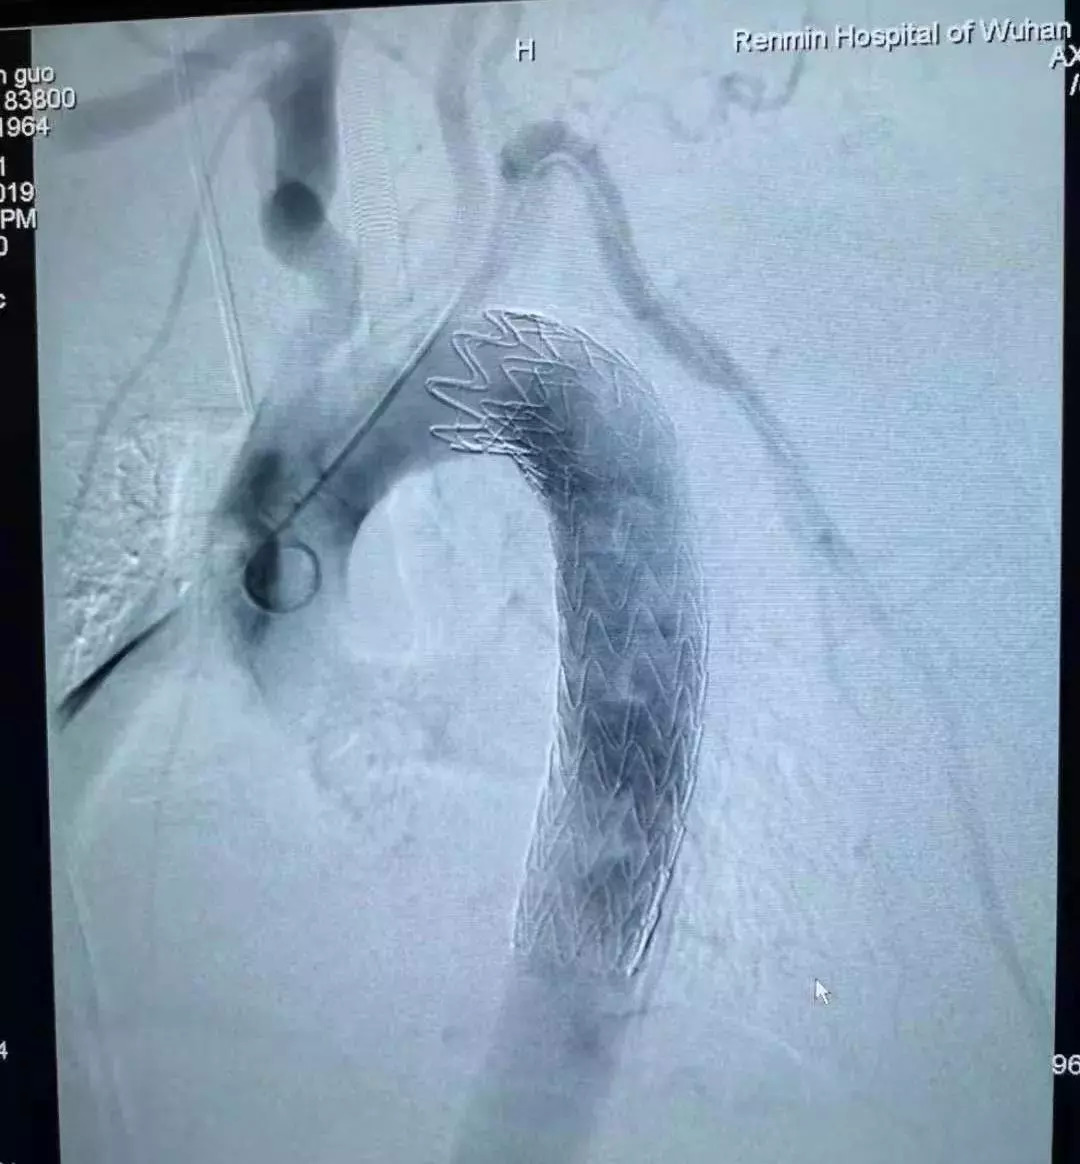

29 日下午,老林被推入导管室。实施麻醉后,心血管外科的医生将主动脉支架植入老林的体内,堵住已经糜烂的血管缺口。

主动脉支架

图片来源:武汉大学人民医院